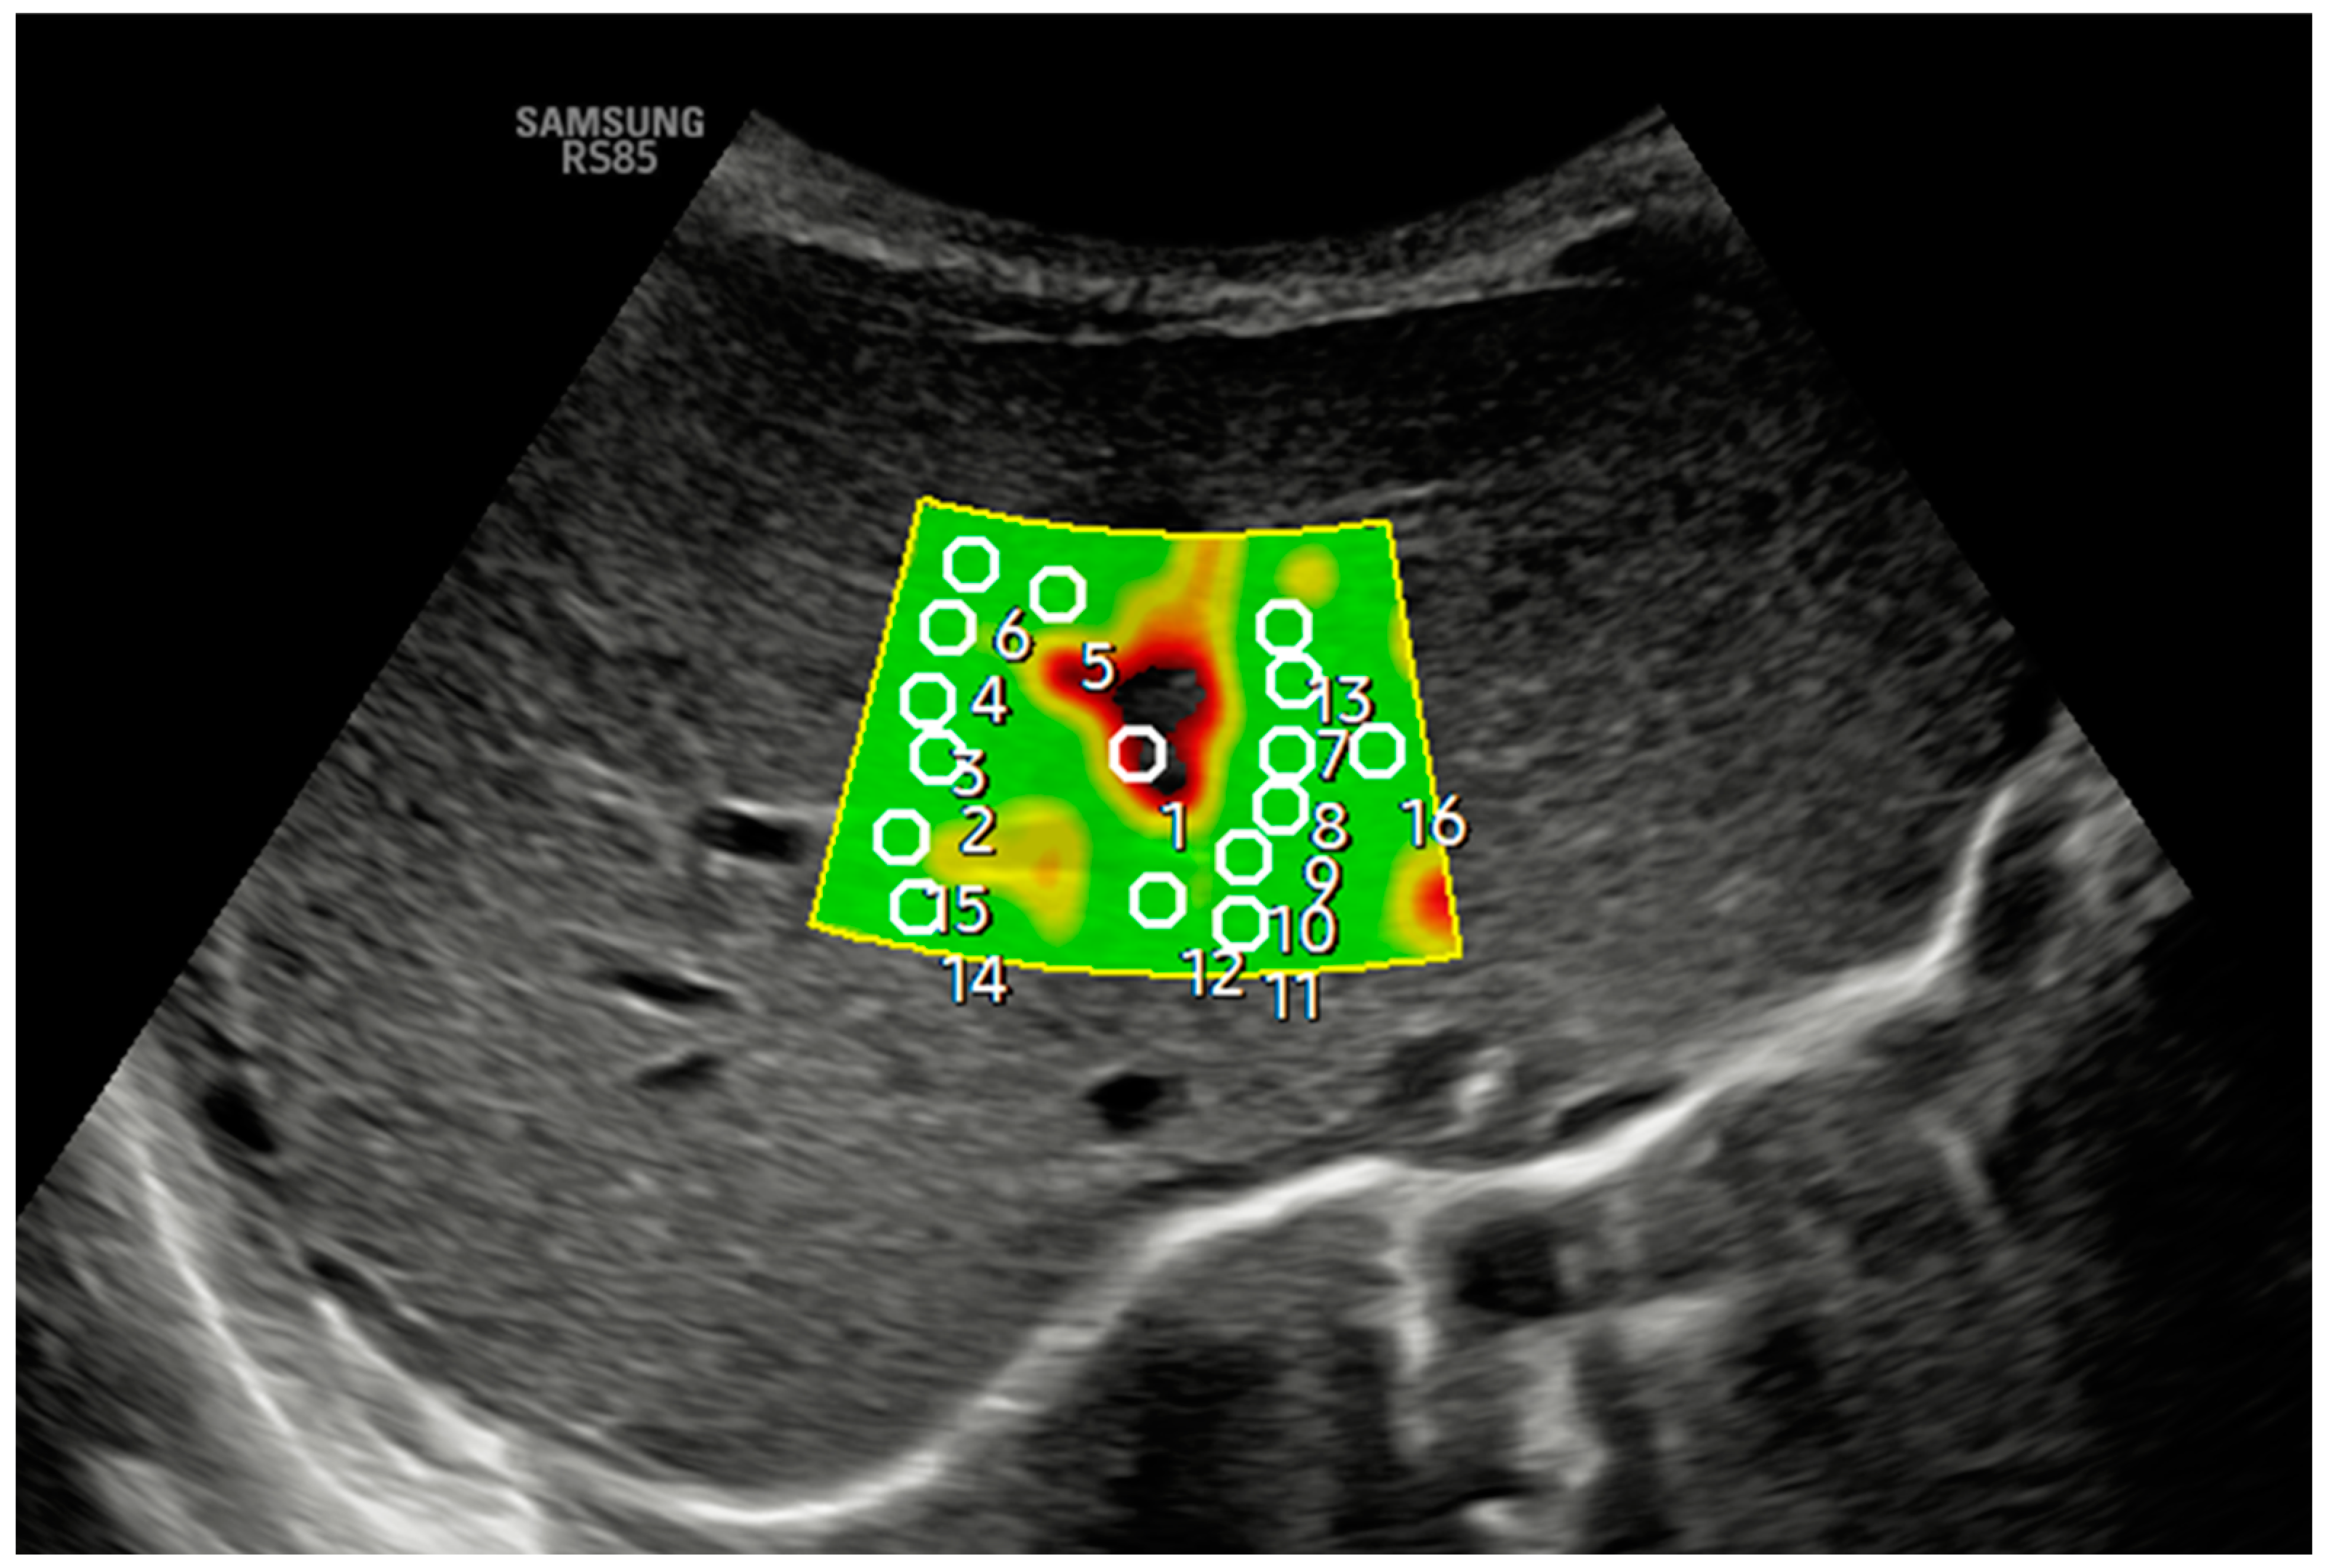

2. Technique